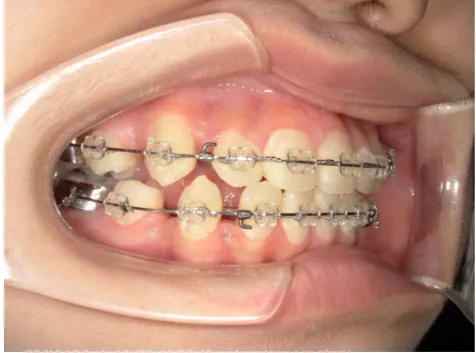

治療中⑧高1:15y11m 抜歯治療中

治療中⑨高2:17y1m 抜歯治療中

治療後⑩高2:17y7m 抜歯治療終了